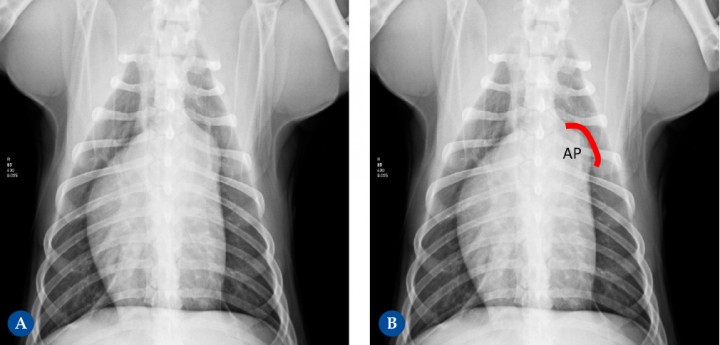

<p>Perro macho castrado de 2,5 años de edad. Se le detecta un soplo de grado I-II. (<strong>A</strong>) Proyección ventrodorsal. (<strong>B</strong>) Diagrama donde se marca sobre la imagen A la proyección anatómica de la arteria pulmonar (AP) . En la radiografía se visualiza un abultamiento (“knuckle”) en el área de proyección anatómica del tronco de la arteria pulmonar (línea roja), según la analogía del reloj entre la 1 h y las 2 h. Dicho paciente fue diagnosticado mediante estudio ecocardiográfico de estenosis pulmonar valvular, con gradiente de estenosis moderada. Este engrosamiento que se observa es debido a la dilatación post-estenótica.</p>

Figura 7

Perro macho castrado de 2,5 años de edad. Se le detecta un soplo de grado I-II. (A) Proyección ventrodorsal. (B) Diagrama donde se marca sobre la imagen A la proyección anatómica de la arteria pulmonar (AP) . En la radiografía se visualiza un abultamiento (“knuckle”) en el área de proyección anatómica del tronco de la arteria pulmonar (línea roja), según la analogía del reloj entre la 1 h y las 2 h. Dicho paciente fue diagnosticado mediante estudio ecocardiográfico de estenosis pulmonar valvular, con gradiente de estenosis moderada. Este engrosamiento que se observa es debido a la dilatación post-estenótica.